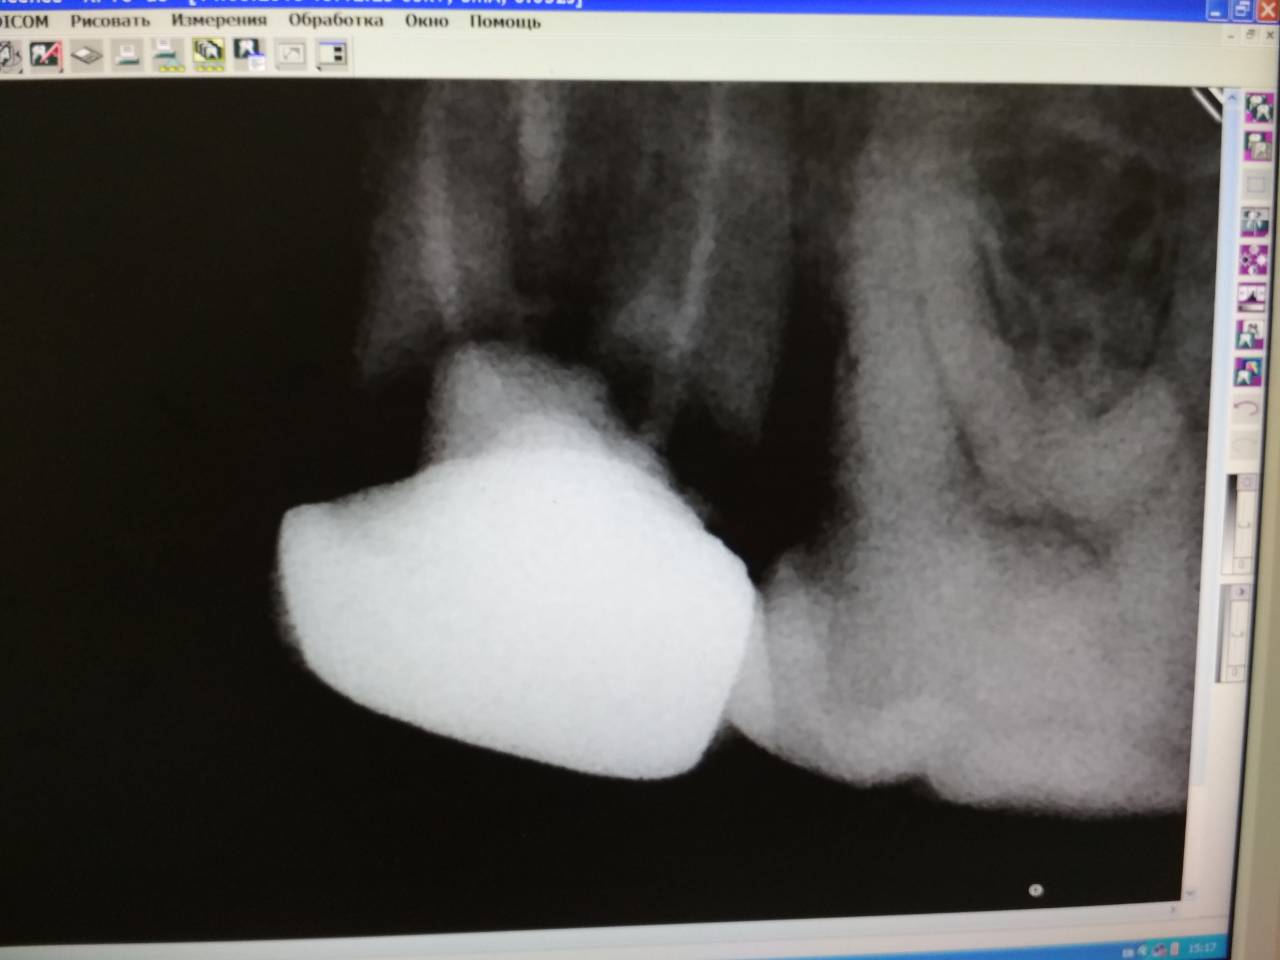

Привожу снимок , который мне сделали.

Цитата Сообщение от Deymos77 Посмотреть сообщение

Здравствуйте, ув.специалисты!

Зуб необходимо удалять, поскольку под коронкой все разрушено.

Я не хочу потерять жевательный зуб и прошу вашего совета, что можно сделать?!

От себя добавлю: коронка , как и сам зуб стоят "мертво", никаких пошатываний зуба при попытке его покачать нет.

Заранее благодарен за ответ и совет!

Вложение 12835628

сделайте еще один прицельный снимок.... по этому мутному отпечатку - под коронкой каждый корень отдельно стоит и держится друг за друга исключительно с помощью набившейся под коронку пищи или честного слова....